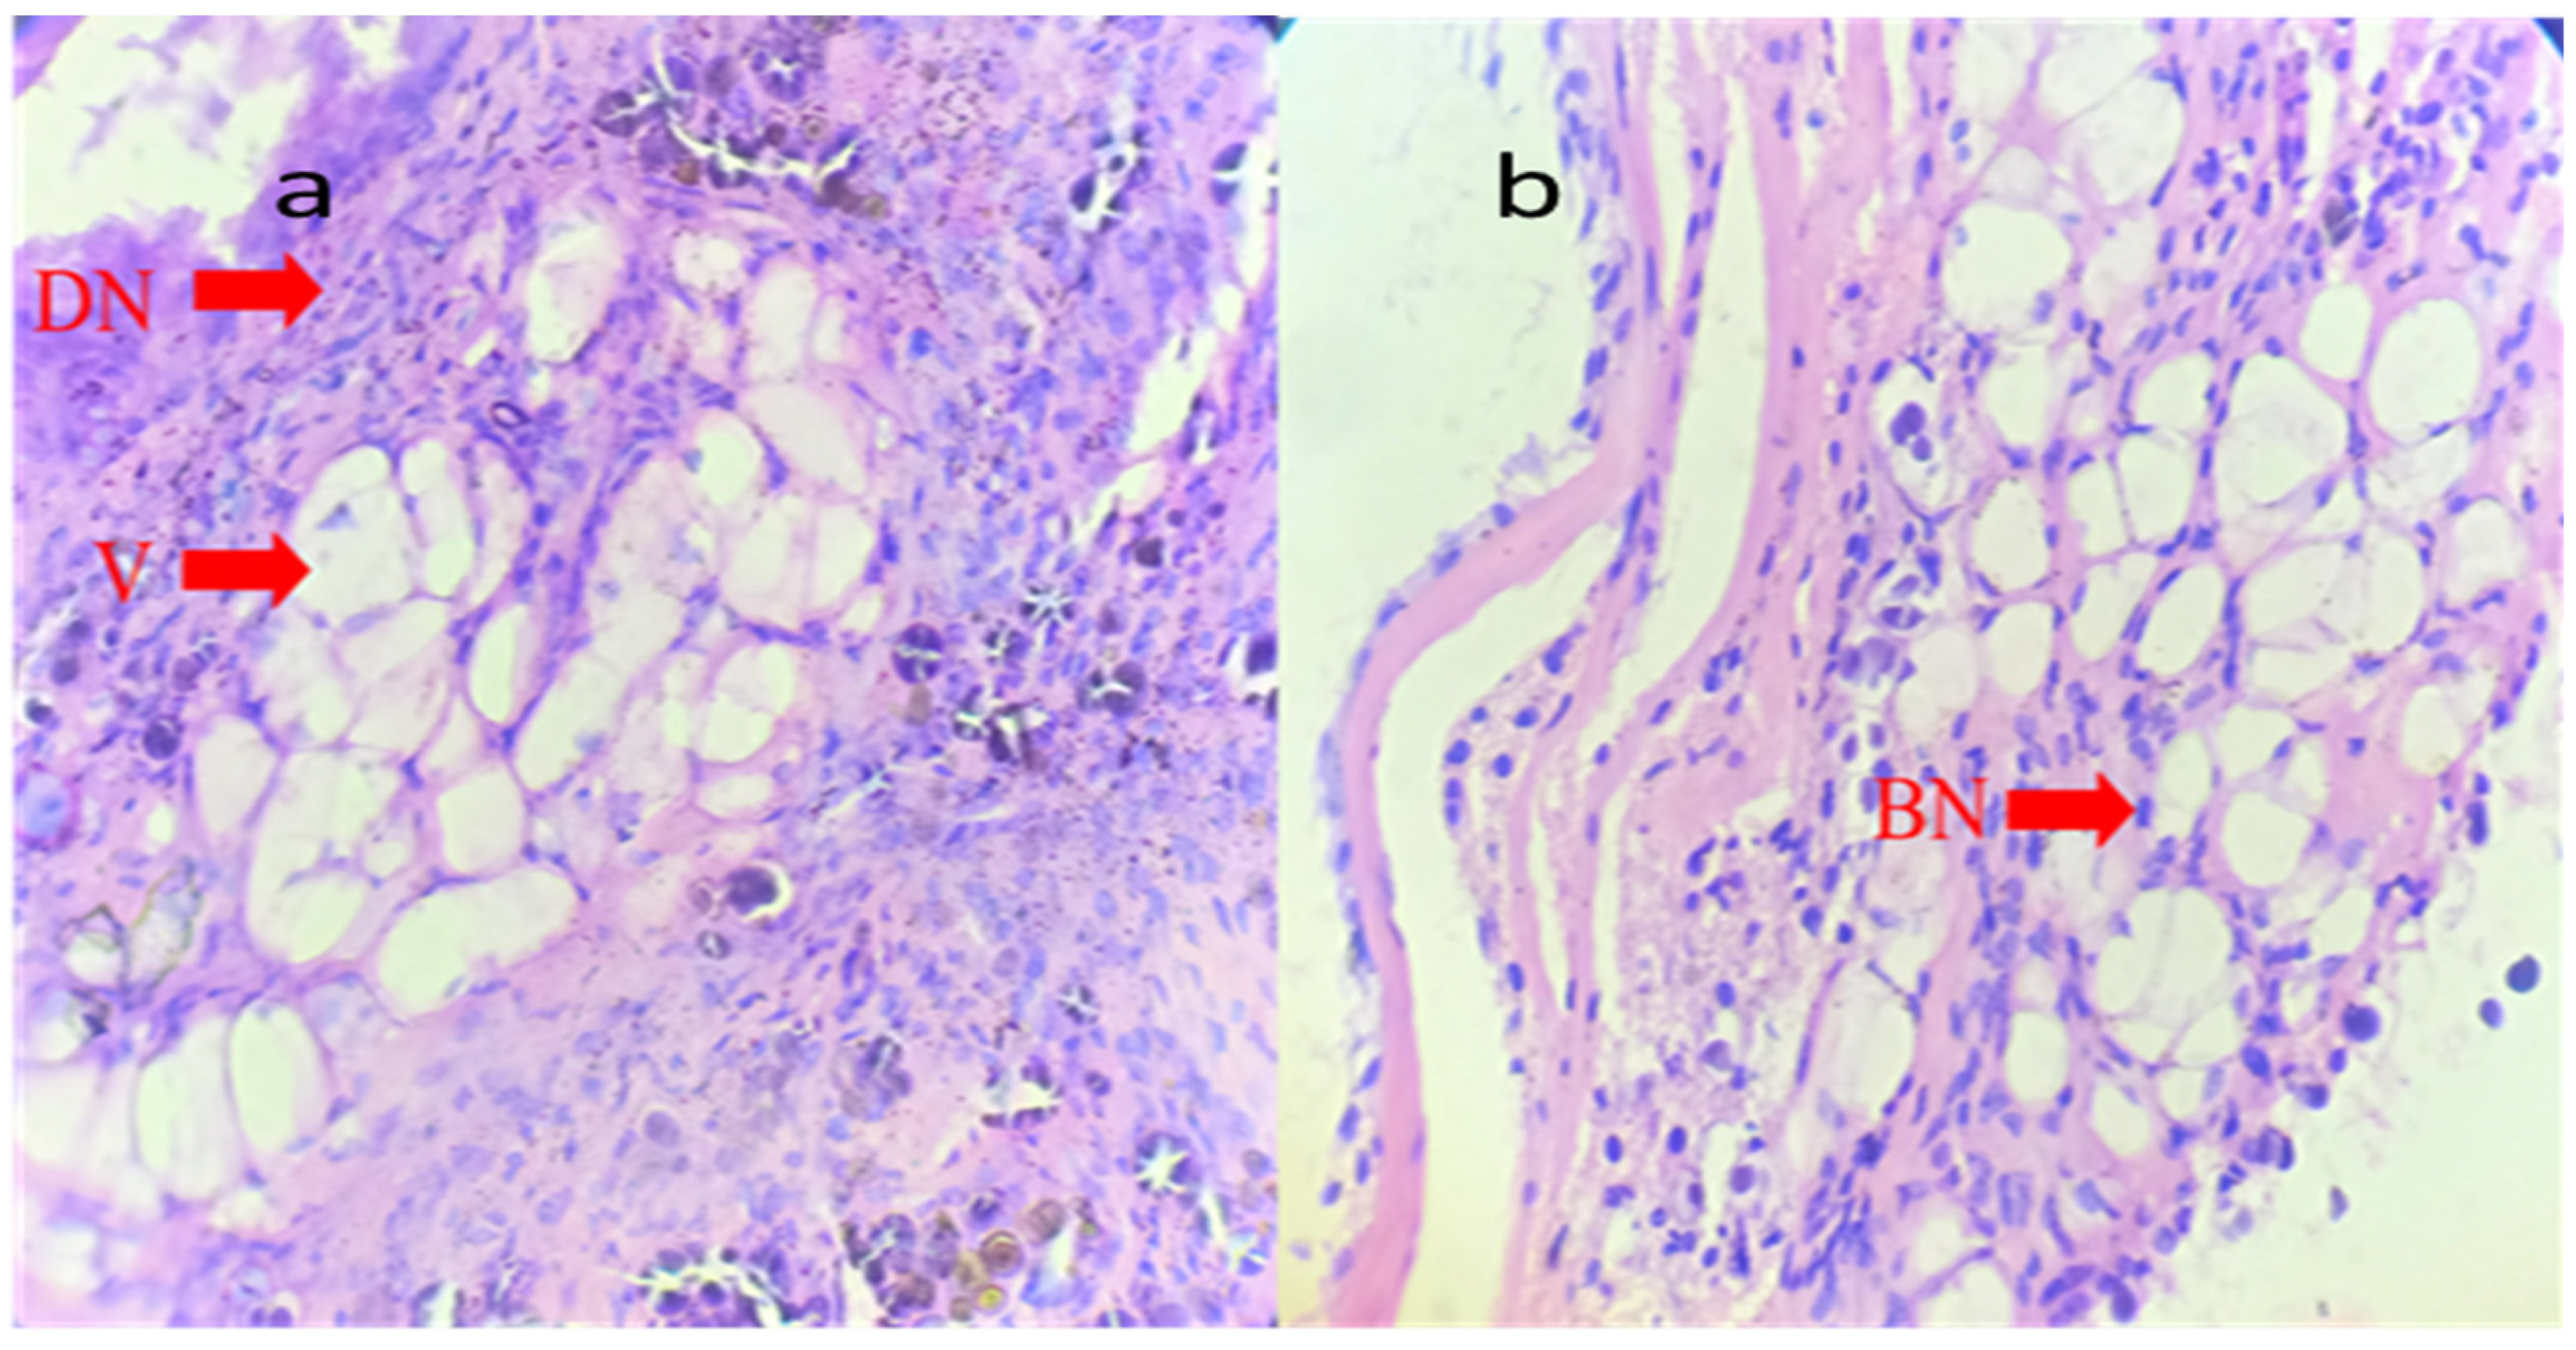

2.5. Histopathology

4.5. Histopathology